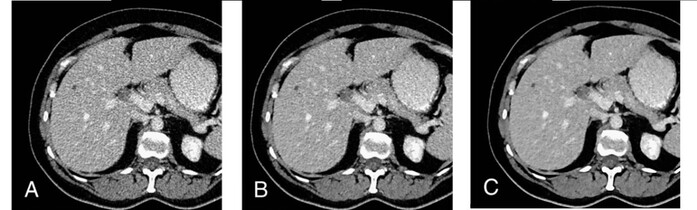

| ▲각 FBP(A), SAFIRE(B), ADMIRE(C) 기술 적용 예시 |

소마톰 고 탑은 신규 버전부터 인텔리전트 통계 모델을 활용해 영상의 노이즈 및 아티팩트를 제거하는 어드마이어 반복 재구성법을 사용한다. 해당 기술을 통해 적은 방사선량만으로도 영상 내 저밀도의 조직도 더욱 쉽게 구별 가능하고 각 신체조직별 선명도와 모습을 다양하게 확인할 수 있다.